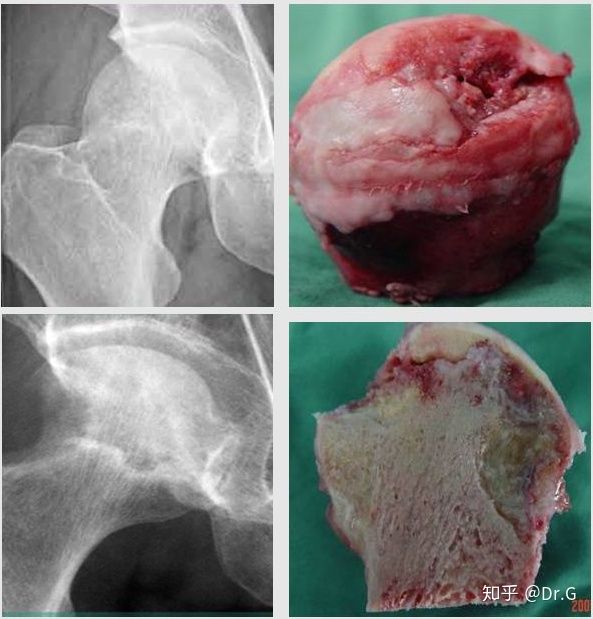

坏死的股骨头X线表现

股骨头坏死患者的早期临床症状不明显,也无明显X线表现,多数患者仅出现髋部疼痛不适,应与腰部疾病相鉴别。此阶段,股骨头内坏死,压力升高,逐渐出现空洞及硬化。

随着病情进展,股骨头逐渐塌陷,患者出现疼痛、活动受限、跛行、局部压痛、患肢短缩、肌肉萎缩等症状。